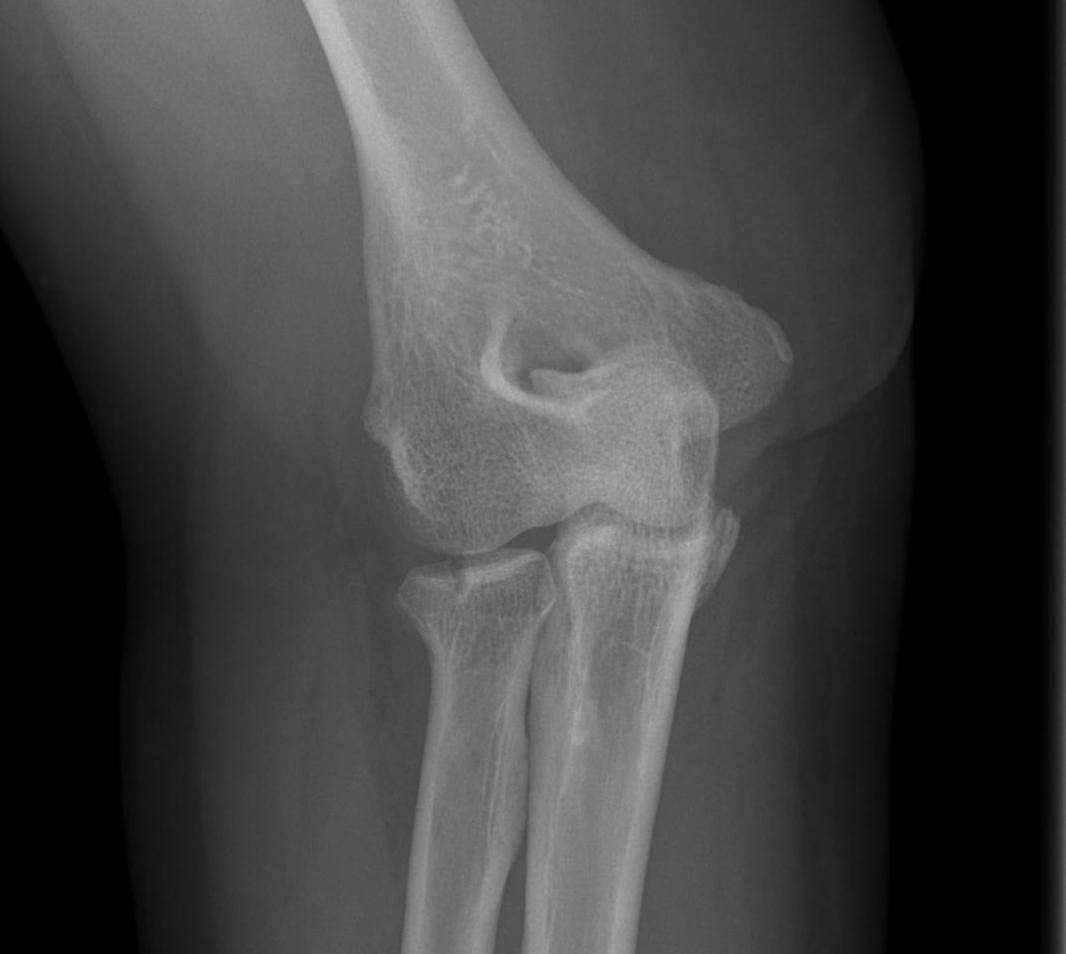

Type 4: Radial head fracture with elbow dislocation

Type 4 radial head fractures